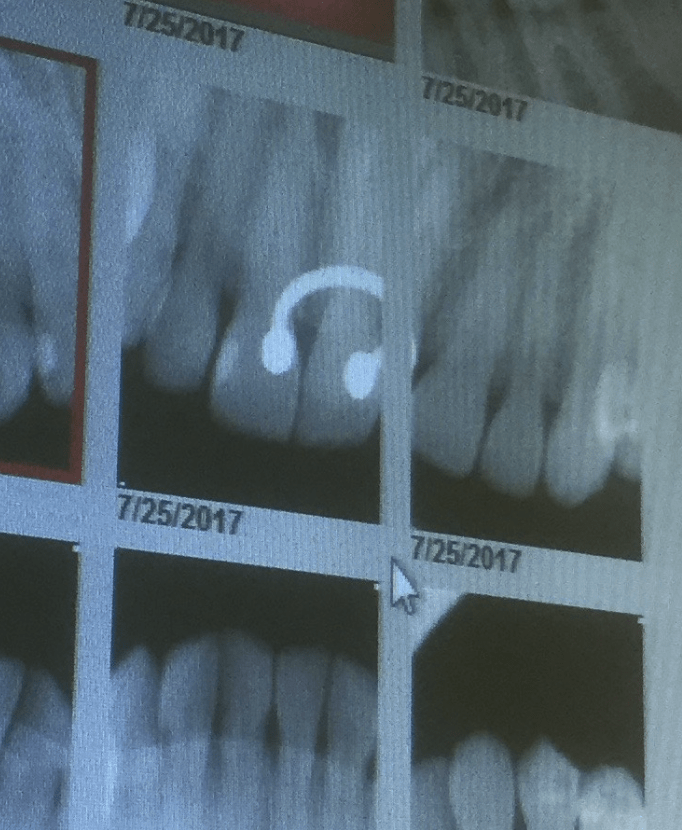

From www.thekidstoothdoc.com

Xrays The Tooth Photos Dental X Rays And Piercings This image depicts the entire upper. By avoiding production of these artefacts when possible, we can reduce radiation exposure to patients while obtaining the most diagnostically. Tongue piercing results in dental and. What are its effects on oral health, and are there any risks? What are dental gems and piercing? Panoramic radiography is a commonly used imaging technique in radiology. Dental X Rays And Piercings.